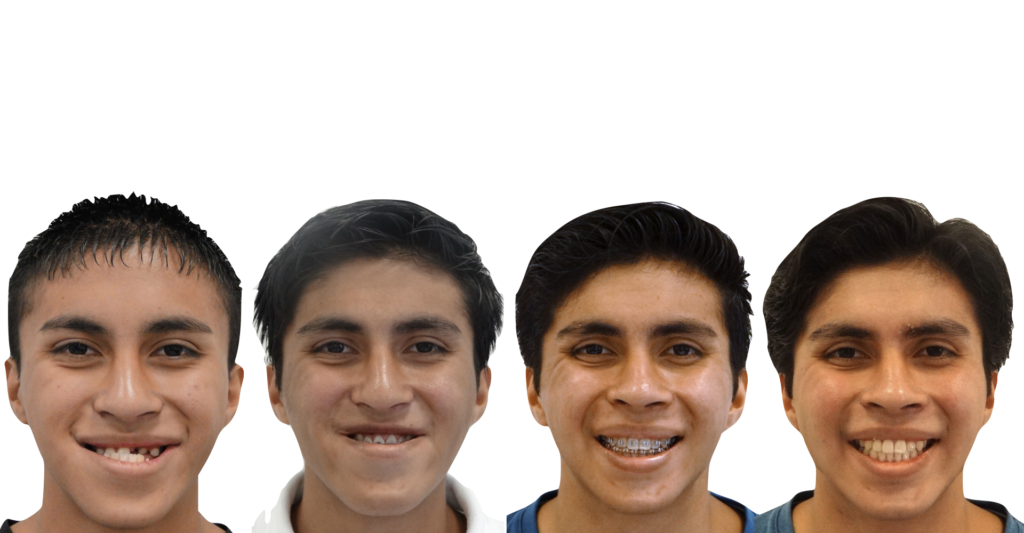

El siguiente caso clínico se trata de un paciente masculino de 18 años (al concluir su

tratamiento). Es un caso Orto/Quirúrgico complejo, donde el paciente presentaba una clase

ósea III debido a una hipoplasia maxilar y un aumento en la longitud del cuerpo mandibular,

ademas de presentar un biotipo dolicofacial (crecimiento de la cara hacia abajo). Este caso fue uno de los primeros casos quirúrgicos en concluir el Dr Quijada cuando aun era residente de la especialidad hospitalaria, donde hubo un trabajo en conjunto.

La primer fase que fue una expansión palatina y tracción de múltiples piezas incluidas en maxilar fue realizada por la Dra Scarlett Escobar, y posteriormente fue heredado el caso al Dr Francisco Quijada para su planeación y tratamiento Ortodóncico/Quirúrgico, una vez concluido la fase de Ortodoncia, estaba listo para la fase Quirúrgica, trabajando en conjunto con el servicio de Cirugía Maxilofacial, una vez concluida la cirugía el paciente estuvo listo para concluir su tratamiento y gozar de una fantástica mejoría en la estética facial, dental y una correcta función oral.

Paciente masculino con prognatismo mandibular severo y discrepancia esquelética Clase III. Presentaba mordida cruzada anterior, dificultad para masticar y alteración estética marcada. Se realizó tratamiento orto-quirúrgico con preparación ortodóncica y cirugía bimaxilar. El resultado final fue una oclusión funcional estable y una armonía facial significativa.

- Diagnóstico : Clase ósea III por hipoplasia maxilar

- Año : 2012